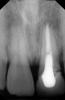

annda Опубликовано 9 января, 2010 Поделиться Опубликовано 9 января, 2010 (изменено) даже на этом снимке трещину видно(даже не трещину ,а линию перелома),по диагонали,прямо под ногой вкладки.Удаление. Изменено 9 января, 2010 пользователем annda Ссылка на комментарий

Alexey2010 Опубликовано 9 января, 2010 Автор Поделиться Опубликовано 9 января, 2010 (изменено) "даже на этом снимке трещину видно(даже не трещину ,а линию перелома),по диагонали,прямо под ногой вкладки" Разве перелом не должен быть виден на самом корне а не в канале? (может быть это просто следы от расцементировки вкладки?)Уже 5 врачей ставят разные диагнозы, неужели нет точного способа определения наличия перелома? Очень не хотелось бы "случайно" по ошибке удалить здоровый корень. Изменено 9 января, 2010 пользователем Alexey2010 Ссылка на комментарий

annda Опубликовано 9 января, 2010 Поделиться Опубликовано 9 января, 2010 (изменено) "даже на этом снимке трещину видно(даже не трещину ,а линию перелома),по диагонали,прямо под ногой вкладки" Разве перелом не должен быть виден на самом корне а не в канале? (может быть это просто следы от расцементировки вкладки?)Уже 5 врачей ставят разные диагнозы, неужели нет точного способа определения наличия перелома? Очень не хотелось бы "случайно" по ошибке удалить здоровый корень.Компьютерная томограмма вам точно ответит на этот вопрос.Лично я на самом корне и вижу. Изменено 9 января, 2010 пользователем annda Ссылка на комментарий